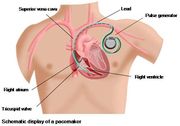

| 17:54, 5 August 2012 | SchematicImg.jpg (file) |  |

50 KB | 2 | |